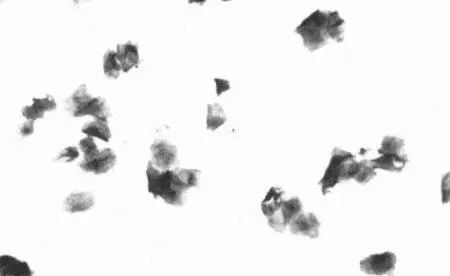

Вагинальная цитология (фиг. 4.5) обнаруживает поверхностные ороговевшие клетки, причем степень ороговения не изменяется до конца проэструса. Концентрация прогестерона сохраняется на базальном уровне. УЗИ обнаруживает увеличенные (более 1 см) неовулировавшие фолликулы. Для подтверждения диагноза проводят лапаротомию.

Фиг 45 Вагинальная цитология суки с кистами яичников Проэструс начался 34 - фото 29

Фиг. 4.5.

Вагинальная цитология суки с кистами яичников. Проэструс начался 34 дня назад. Выделения типичны для конца проэструса и содержат поверхностные клетки (см. Приложение)